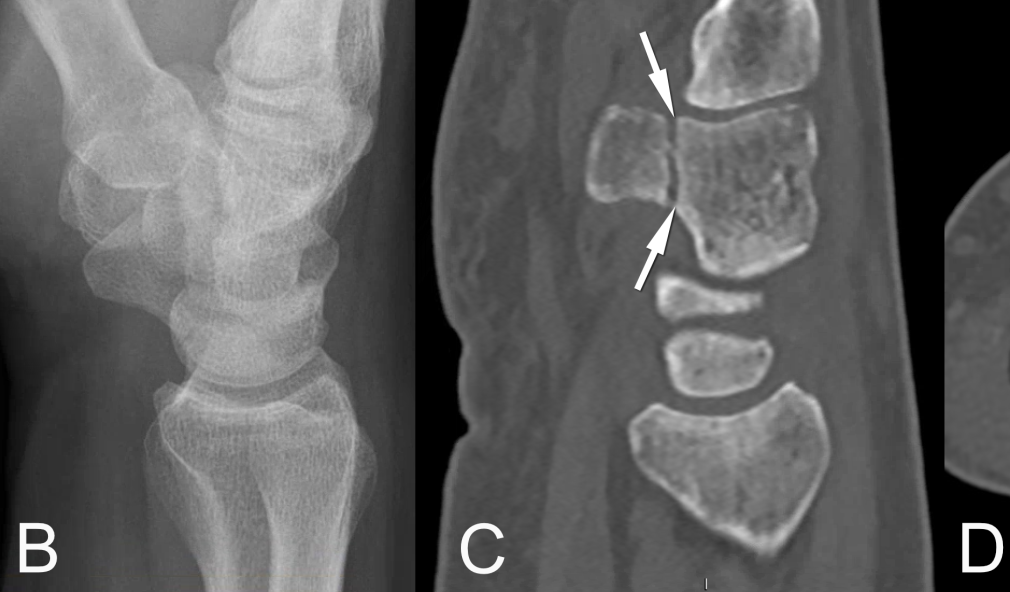

Bildgebung Fraktur der Basis des Hamulus ossis hamati

Sturz auf die Hand: Zuerst Röntgen – wann CT oder MRI?

Auf was ist bei einer Röntgenaufnahme bei einem Trauma an Finger, Mittelhand oder Handgelenk zu achten? Und in welchen Fällen machen eine CT- oder MRI-Aufnahme Sinn? Ein kurzer Ratgeber, wie im Einzelnen vorgegangen werden kann und wie bereits in der Praxis eine erste sinnvolle Bildgebung in die Wege geleitet wird.